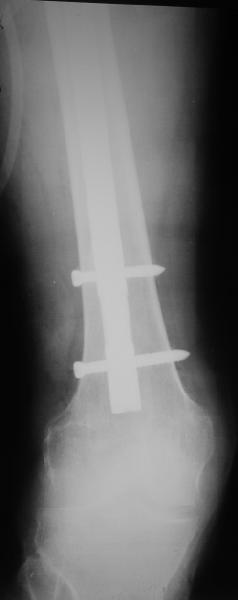

Female, rheumatoid, THA in 2003, car accident in 2006, failed plating. Nailing in Oct 2007. The nail is solid with hollow proximal part where the stem is docked. Last images are in 1 year after

nailing.

Спасибо за обсуждение. После нескольких дней тракции аппаратом сделали. Попытка закрытой репозиции не удалась из-за смещения по ширине, мешали фрагменты цемента. После их удаления репозиция получилась. Еще убрали немного цемента с ножки по латерльной стороне, чтобы обнажить 40-50 мм ее дистальной части, для плотной посадки гвоздя. Дальнейшее введение гвоздя было несложным. Протез показался нам стабильным в проксимальной части как латерально, так и медиально. Картинки в приложении.

THX for the discussion. After few days of traction by ex-fix the surgery was performed. An attempt of closed nailing was unsuccesful because of fragment translation, which was blocked by cement fragments. After removal of broken cement pieces reduction was reached "automagically". Also some cement from lateral part was removed by

chisel to expose distal 40-50 mm of the stem to allow tight fit of the nail. Further fixation by the nail was pretty easy and straightforward. Images attached. The stem looked stable in its proximal part both laterally and medially. Comments/critics are welcome.